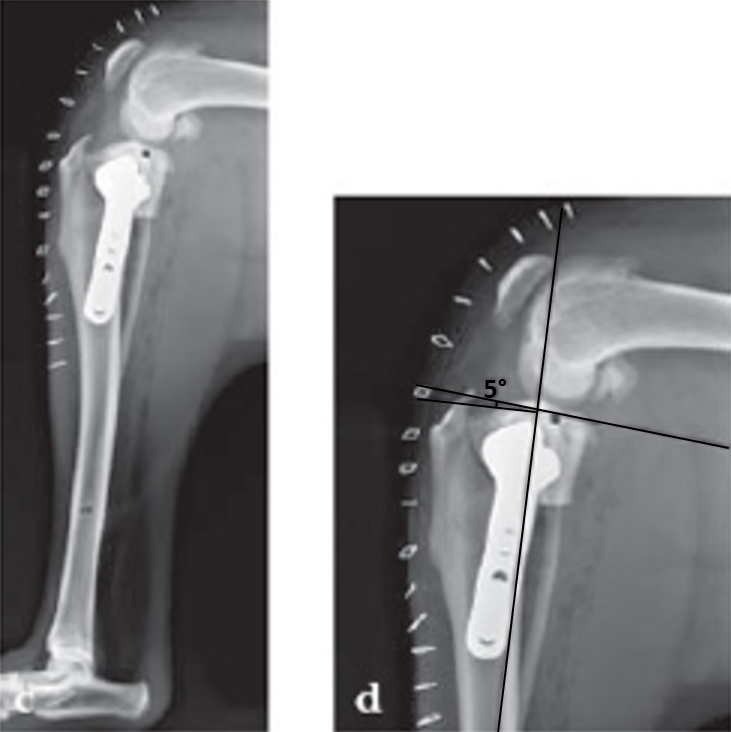

Tibia plateau leveling osteotomy (TPLO) is a surgical procedure developed for the treatment of cranial cruciate ligament deficient stifles in dogs. TPLO is proposed to decrease cranial tibial thrust by controlled rotation of the tibial plateau. Currently, conventional and angular stable plate fixation can be performed to stabilize the cylindrical osteotomy. This study investigated the biomechanical consequences of the procedure including the effect of using either conventional or locking head screws in the tibial plateau fragment.

Eight pairs of cadaveric dog tibiae were instrumented with titanium reference pins in order to track the tibial plateau fragment orientation by means of CT imaging. Position of the tibial plateau was determined for the intact bone, after rotation of the fragment, and after plate application (Fig 1). Bones were pairwise instrumented by an experienced surgeon with TPLO plates using either conventional or locking head screws in the tibial plateau fragment. All specimens were biomechanically tested in physiological orientation using cyclic axial compression at 1000 N for 30.000 cycles. Stiffness at the beginning of the test and plastic deformation of the construct at the end of the test were determined in terms of displacement of the machine actuator.

The conventional screw group revealed a significant larger translation of the fragment towards the plate (P =.006) and a greater variance

in fragment rotation as a result of plate application (Fig 2). However, maximum deviations of the achieved tibial plateau orientation from the preoperatively planned orientation were up to 5 for both groups. The amount of this rotation correlated significantly with the plastic deformation of the construct after testing in the conventional screw group (R = 0.81, P = .005). Neither plastic deformation nor construct stiffness were significantly different between conventional and angular stable plate fixation.

This study demonstrated less variation of the tibial plateau position due to instrumentation with an angular stable TPLO plate. However, the fixation type did not affect the biomechanical stability of the construct. Within the conventional group a higher biomechanical stability can be achieved due to a lower degree of rotation which leads to a larger bony contact between the fragments.